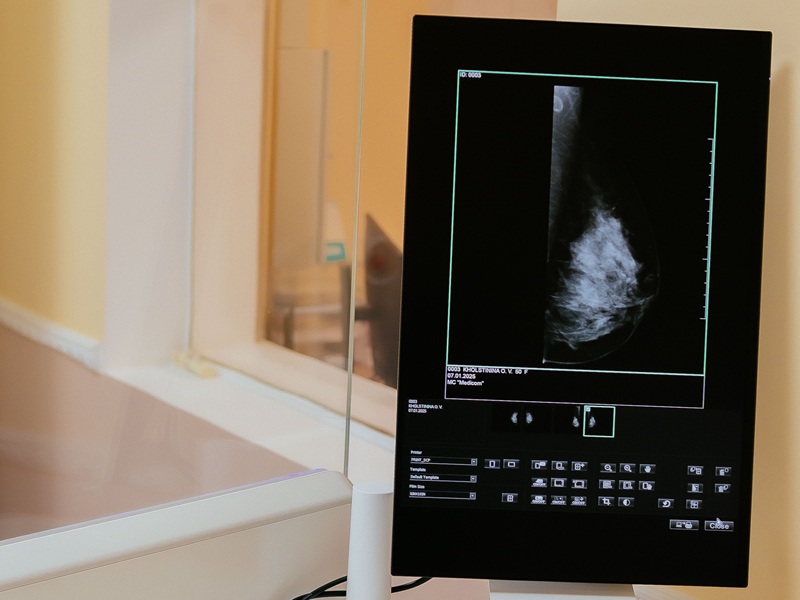

Цифровий мамограф Fujifilm (Японія). Мінімальне променеве навантаження!

У нашій клініці використовується цифрова мамографічна система Amulet Innovality (Fujifilm), яка дозволяє отримати знімки високої роздільної здатності з мінімальним опроміненням.